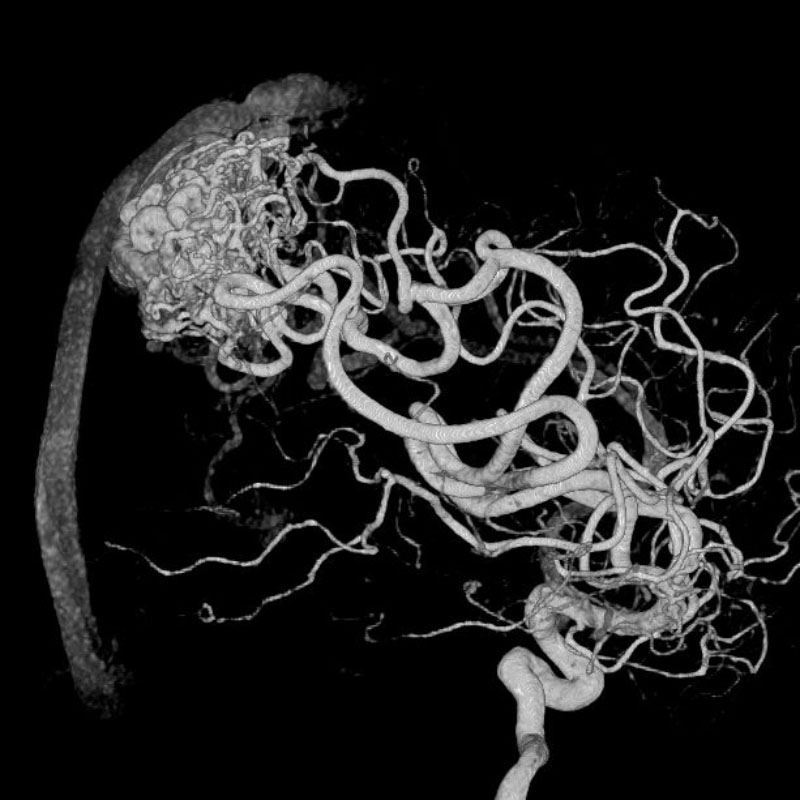

脳動静脈奇形

血管塞栓術

芝野/古谷